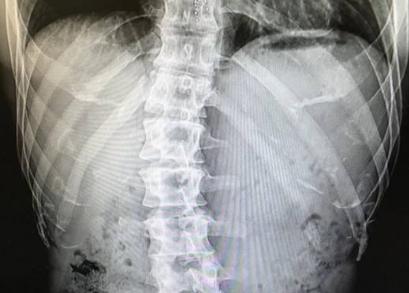

图为金钟国曾在社交媒体晒出自己腰部x

金钟国曾经在访谈类节目《healing camp》中直言,早在中学的时候,金钟国的腰间盘就出现过问题,因此吃了不少的苦头 。

1998年,在turbo时期,因为练舞也受过很严重的腰伤,因为那个时期,金钟国的日程问题,并没及时接受治疗,但是医生告诉他,运动可以减缓他的腰伤,金钟国听进去了,只是没想到从那以后,在至今二十年的时间里,金钟国跟健身房结下了不解之缘。D社狗仔曾经跟踪金钟国的,最后对金钟国总结,只有一句话,不是在健身,就是在去健身的路上。

虽说健身有效的缓解了的金钟国的腰伤,但是98年至今20多年的时间内,金钟国的腰伤,依旧会时不时的复发,并且膏药对如今的他已经没有了任何作用,曾在节目之中表示,一天起床,最大的愿望,就是希望,自己腰会没事,不会有复发的症状。

怎么样?我们在《Running Man》和各大综艺之中看到金钟国的健壮形象其实都是假象而已,真实的金钟国其实这些年一直在接受者腰伤带来的困扰,并没有我们想象中的那么强大。甚至金钟国曾经袒露,因为腰伤曾经考虑过退出《Running Man》。随着时间的推移, 金钟国今年已经四十三岁了,终有一日,他可能会承受腰伤的侵袭没退出《Running Man》,所以有金钟国的《Running Man》看一期少一期,大家好好珍惜吧。